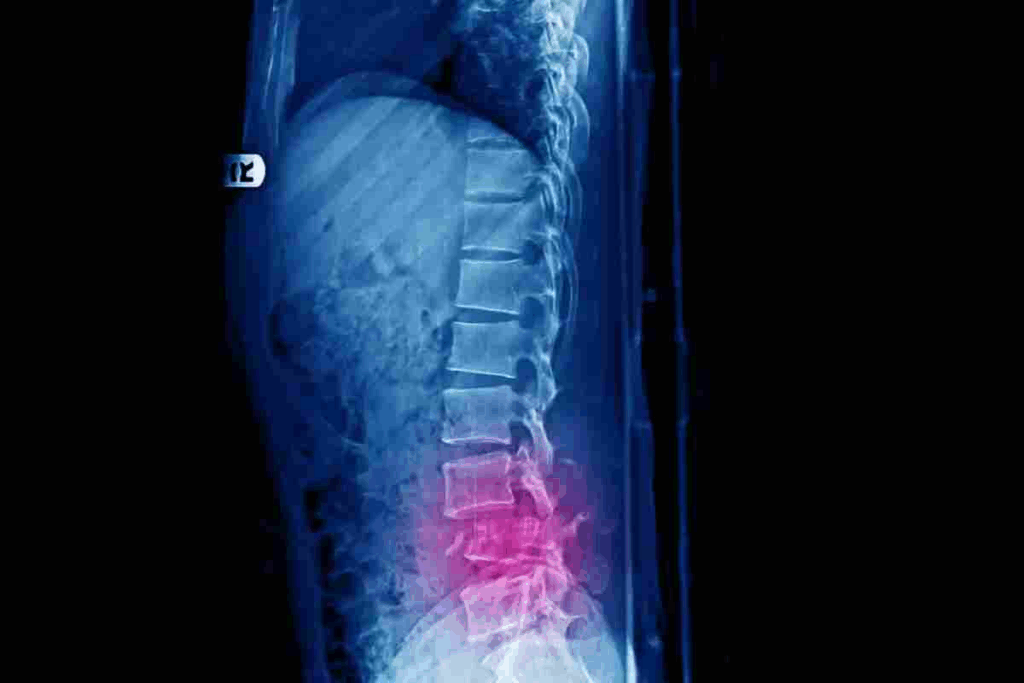

Getting a correct diagnosis for L1 compression fractures is key to finding the right treatment. We know diagnosing these fractures needs a detailed look at both the patient’s health and advanced imaging.

The first step is a detailed medical check-up. We look at the patient’s past health, checking for things like osteoporosis or past fractures. We also do a physical exam to see if there’s any nerve damage or spinal instability.

Key components of the initial evaluation include:

Imaging tests are vital to confirm the diagnosis and see how bad the fracture is. We use X-rays, CT scans, and MRI to get a clear picture of the fracture.

After confirming the diagnosis, we classify the fracture based on its severity. This helps us decide the best treatment and what to expect.

The classification process involves:

By combining the results of the initial medical check-up, imaging, and fracture classification, we get a full picture of the patient’s situation. This helps us choose the best treatment for L1 compression fractures.